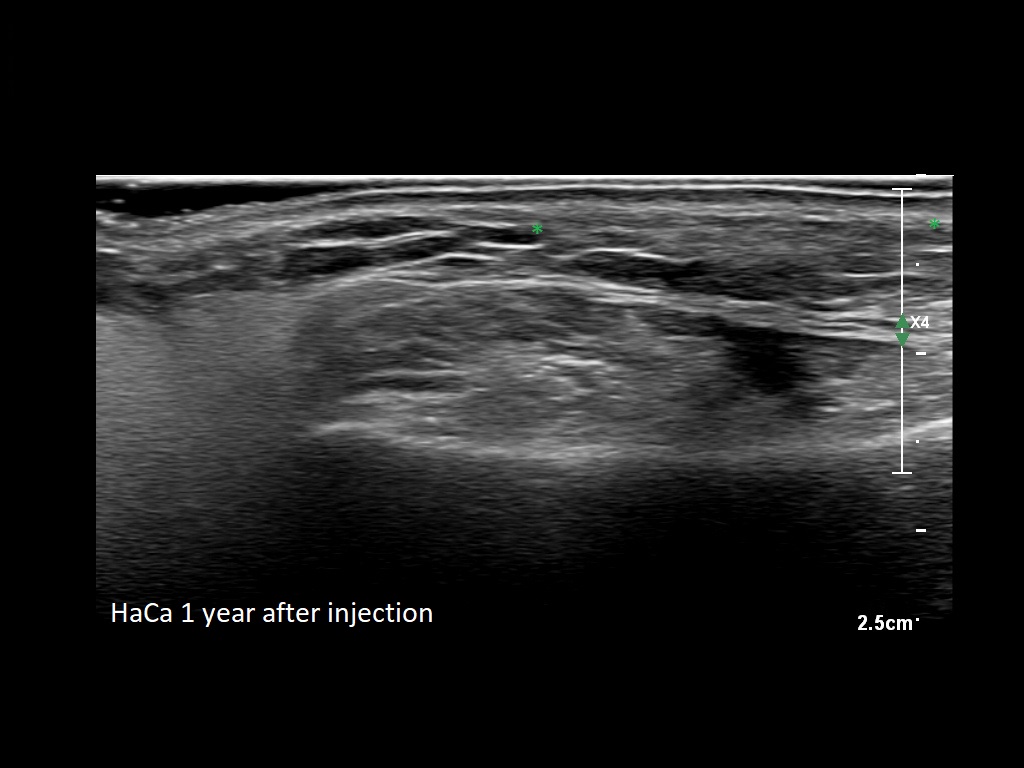

Fillers

Draw in the image on the right where the fillers are located. To check if your answer is correct, please click on the secondary image.

Fillers

Draw in the second image below where the fillers are located. To check if your answer is correct, swipe the first image to the right.

HAca 1a

HAca 1b e